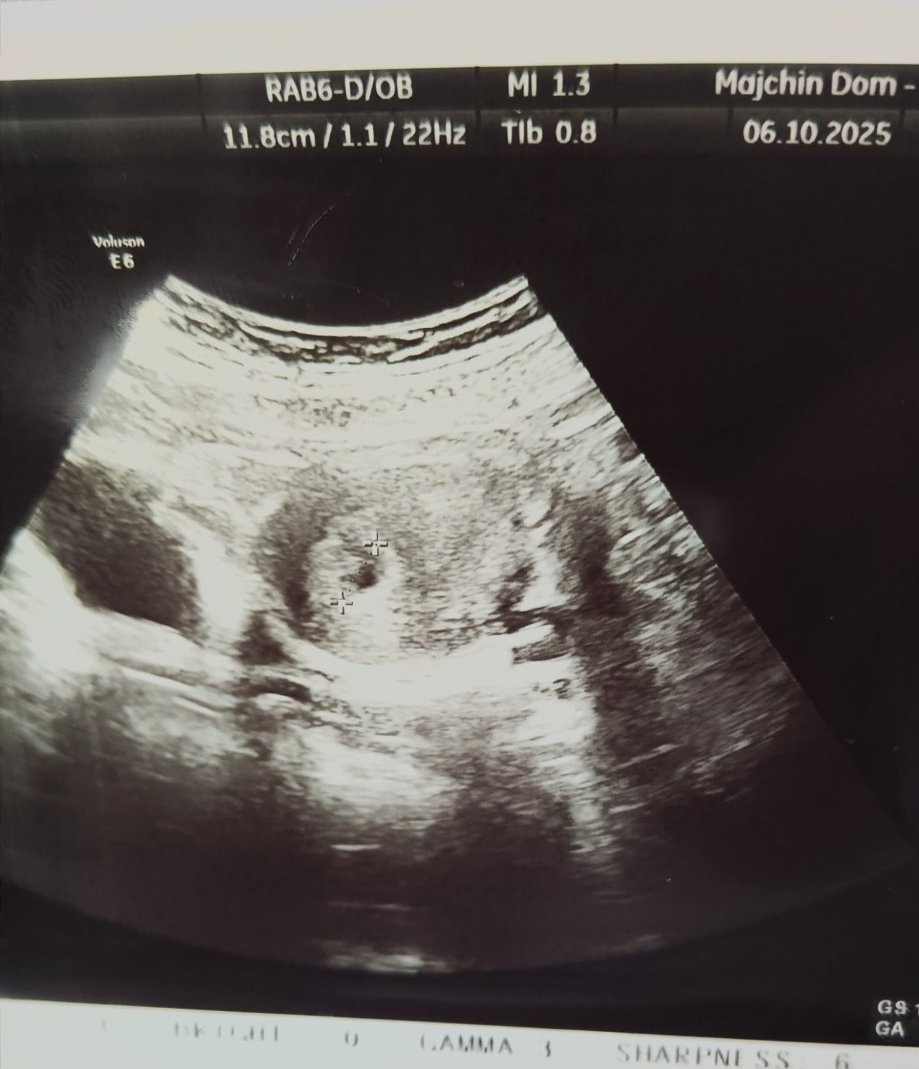

Какво представлява изображението от ехографията на 5-седмична и 2-дневна бременност?